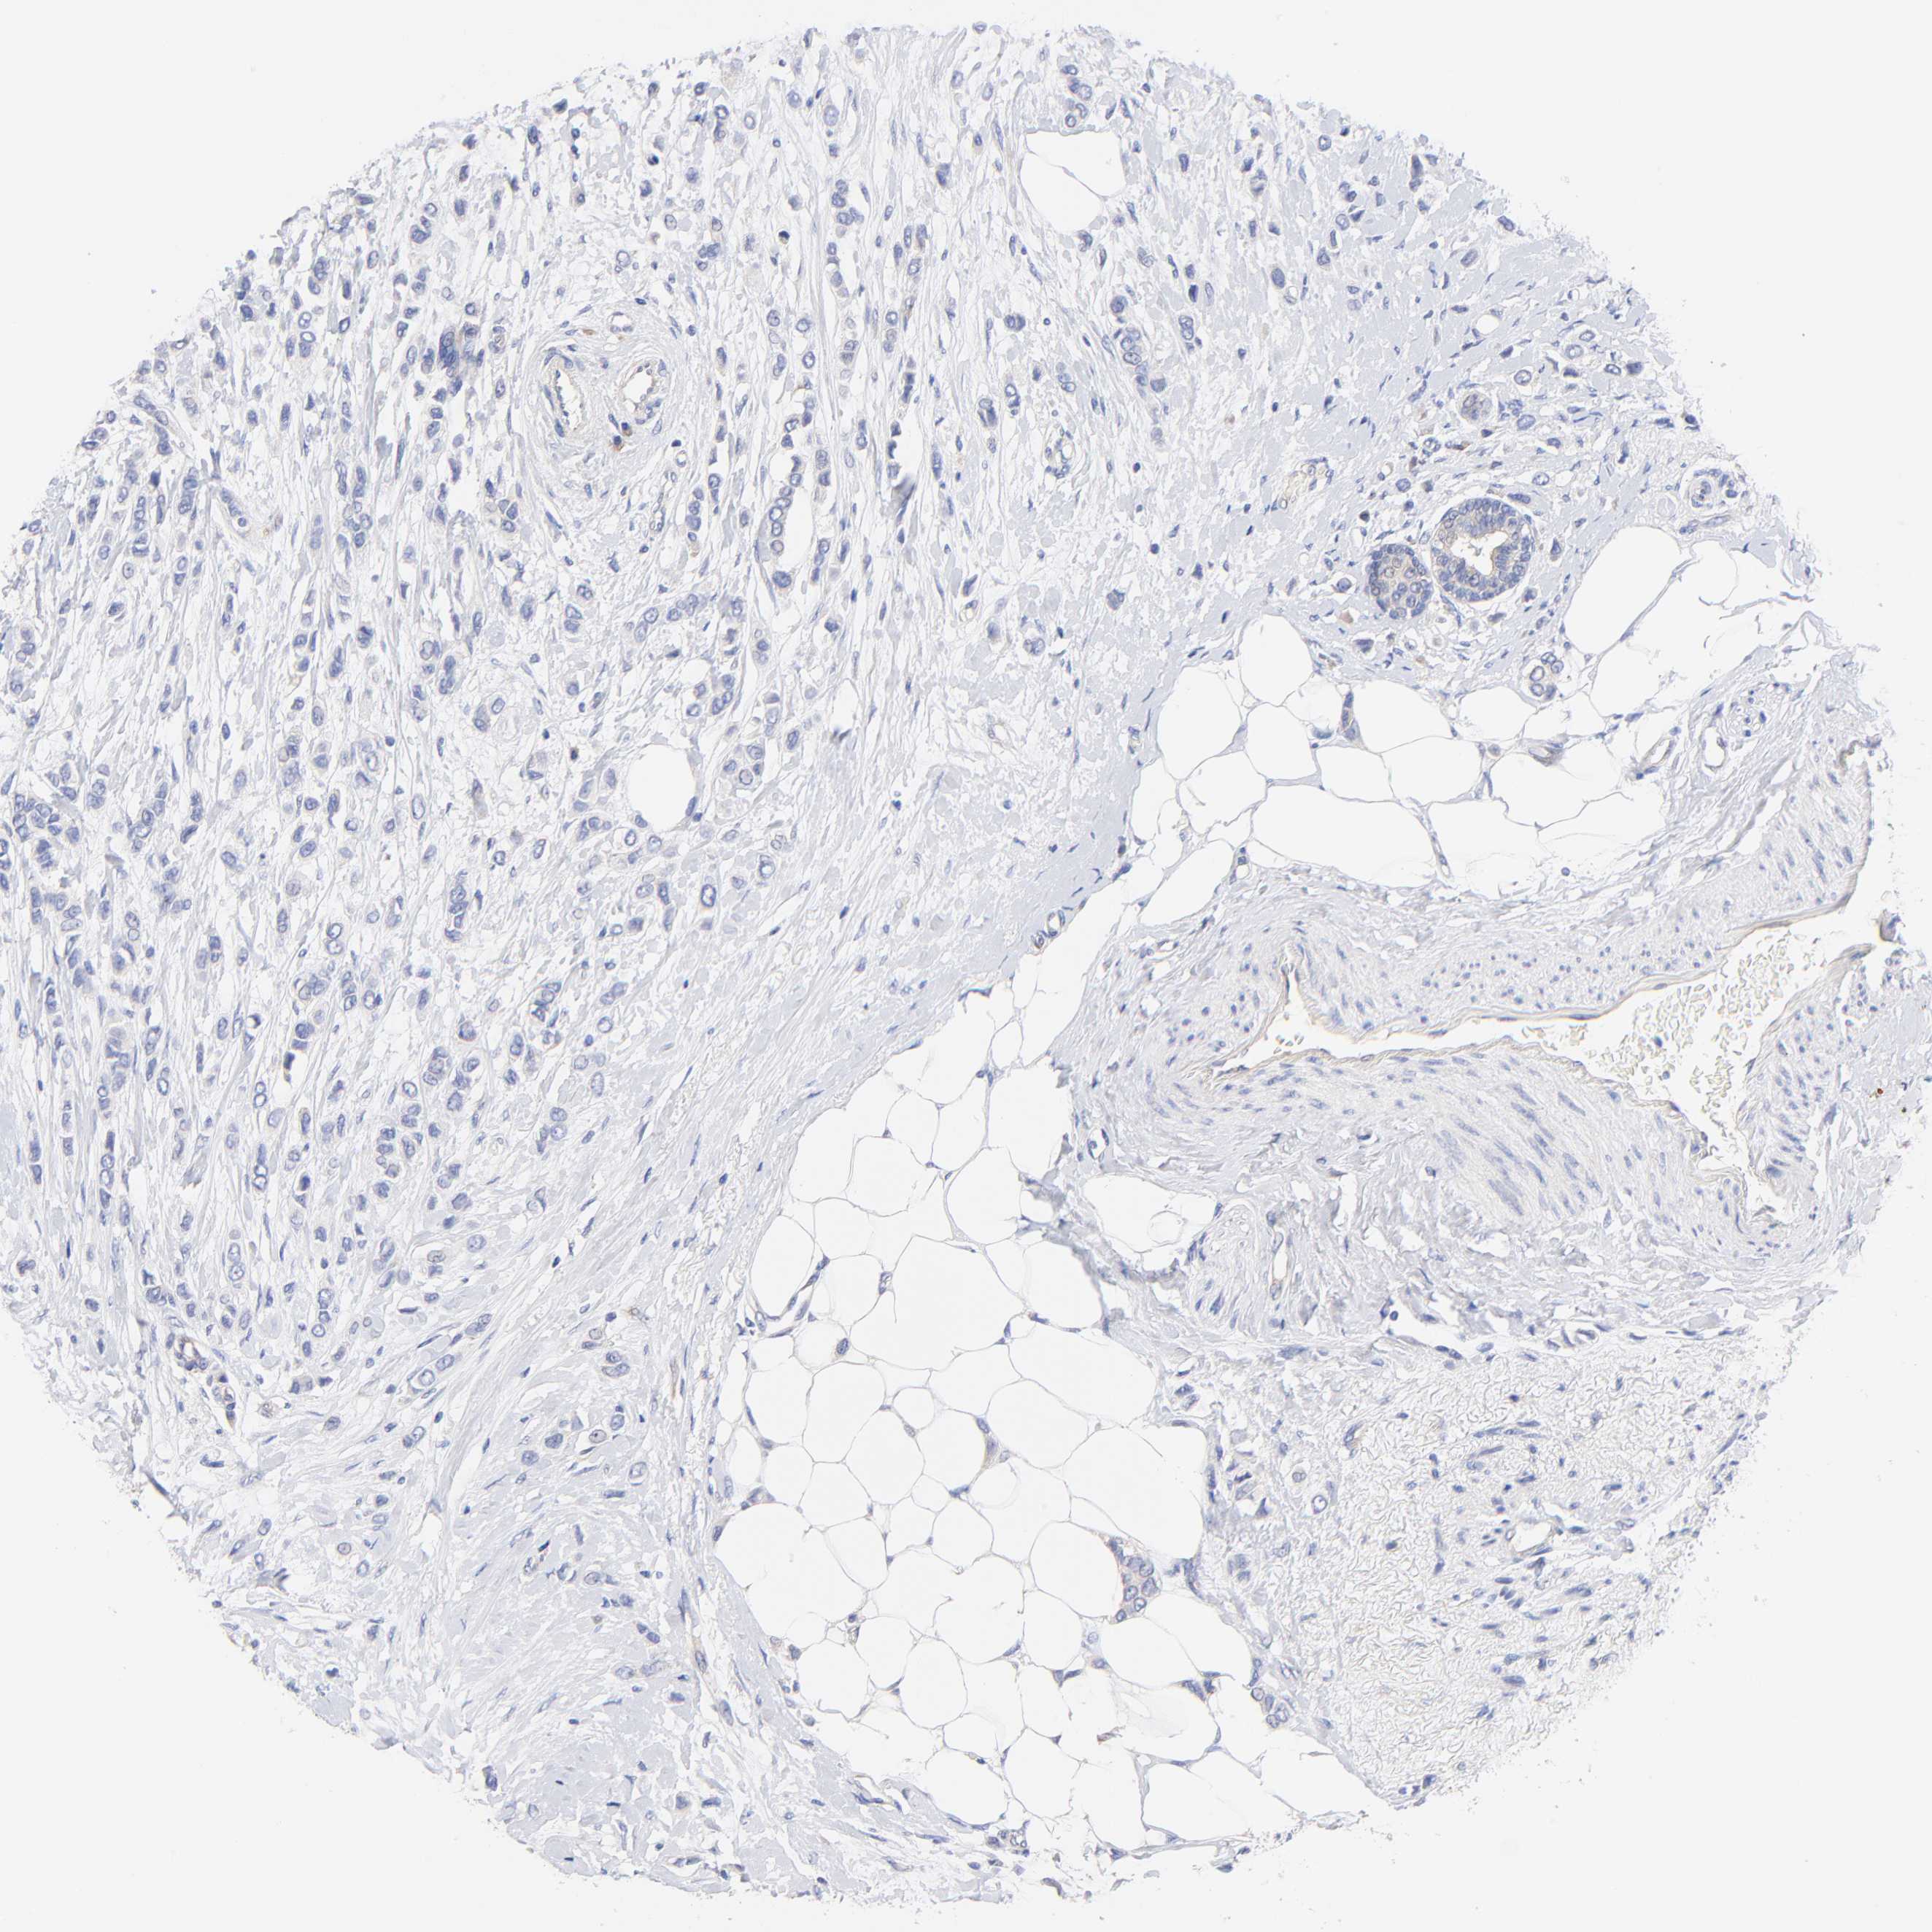

BRCA TCGA BRCA VALIDATION PROTEIN EXPRESSION

ANTIBODIES

AND

VALIDATION